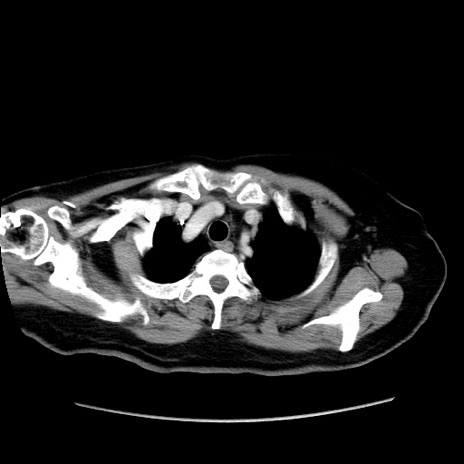

症例19(横断像)

【症例】80歳代女性

【主訴】下腹部痛

【現病歴】約8時間前より下腹部痛の出現あり、救急外来受診。

【既往歴】両側付属器切除

【身体所見】意識清明、下腹部正中に手術痕あり、その部位に一致して圧痛と反跳痛あり。腸蠕動音は亢進。

【データ】WBC 9300、CRP 0.15